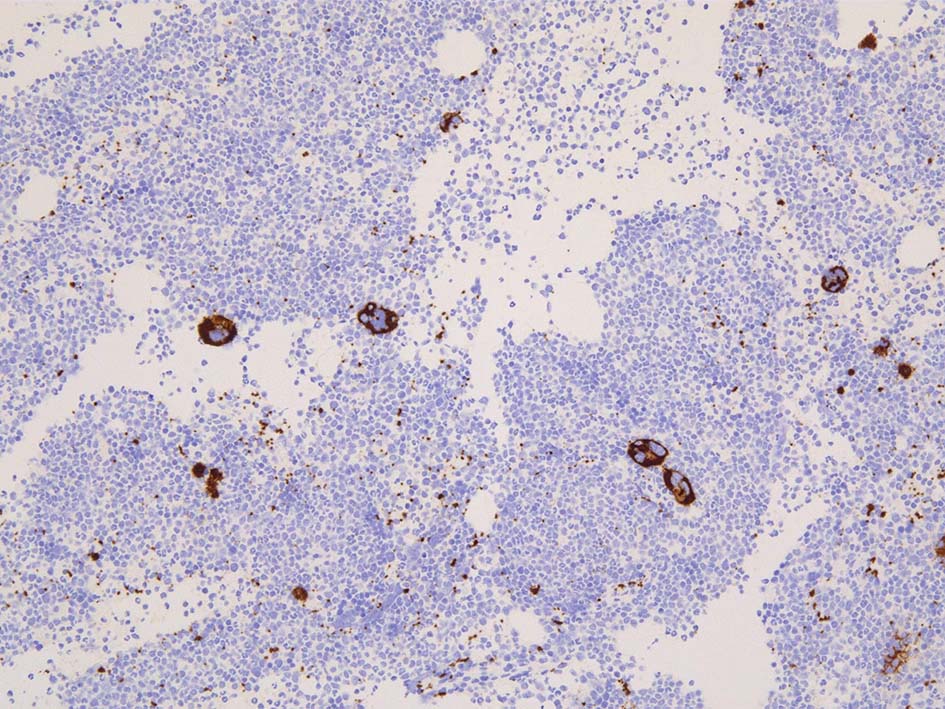

CD42b

- CD42b; microMgkは増加してない. hypercellular marrowであるがMgkの増加はみられない.

免疫染色; CD34, c-KIT, p53染色

本症例ではCD34, C-KIT陽性幼若細胞が増加している. 芽球はcountで4.3%. CD34, C-KITではfocalに 5-10%.